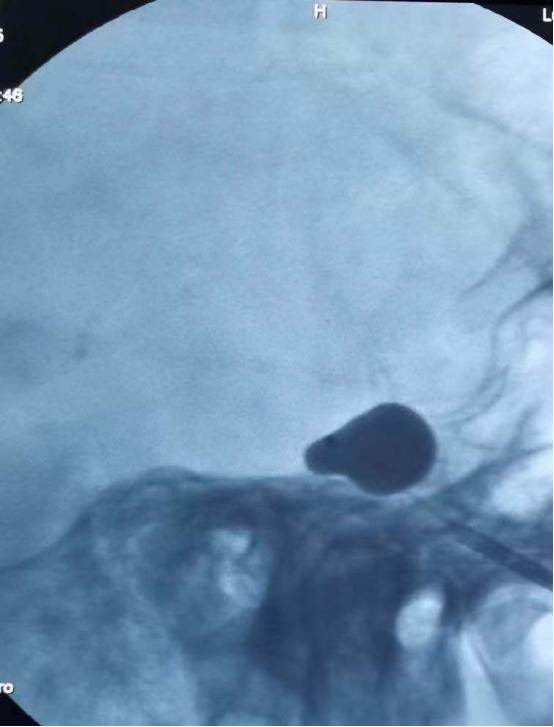

该手术是经面部皮肤穿刺到达三叉神经半月节的部位,通过球囊导管适度压迫,达到控制疼痛的效果。整个创口仅一针眼大小,在我院引进的美国GE双板DSA的影像设备精准定位下完成,该设备一次注射造影剂同时显影正、侧位血管影像,可清晰显示血管造影。

五十分钟后,华安脑科医院神经外科专家团队成功完成经皮穿刺三叉神经半月节球囊压迫术,手术过程中刘奶奶几乎没有疼痛和不适感,术后当天就可下床活动,无皮肤切开,无伤口疼痛,疼痛得到有效缓解。